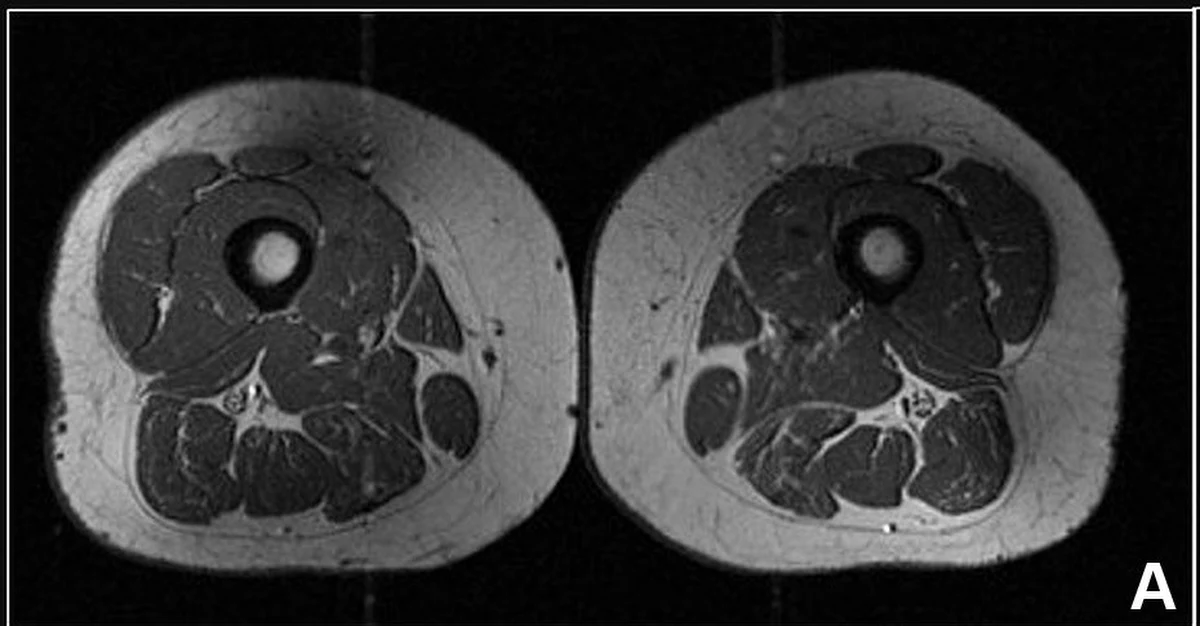

Zdjęcia z rezonansu magnetycznego opublikowane przez naukowców z Uniwersytetu Kalifornijskiego w San Francisco na łamach pisma "Radiology" pokazują, dlaczego warto unikać ultraprzetworzonej żywności.

Na jednym z nich widać coś, co - jak zauważa CNN - może przypominać marmurkowy stek z licznymi drobnymi włóknami tłuszczu. Jest to jednak udo 62-letniej kobiety, która 87 proc. swojego rocznego zapotrzebowania kalorycznego pokrywała, spożywając żywność wysoko przetworzoną.

Naukowcy przeanalizowali dane na temat 615 zdrowych uczestników (średni wiek - 60 lat) projektu Osteoarthritis Initiative, poświęconego chorobie zwyrodnieniowej stawu kolanowego. Stwierdzili, że im więcej ultraprzetworzonej żywności spożywali badani, tym więcej tłuszczu śródmięśniowego mieli w mięśniach ud. Dane wskazują, że dodatkowy tłuszcz może zwiększać ryzyko zwyrodnieniowej choroby kolan.